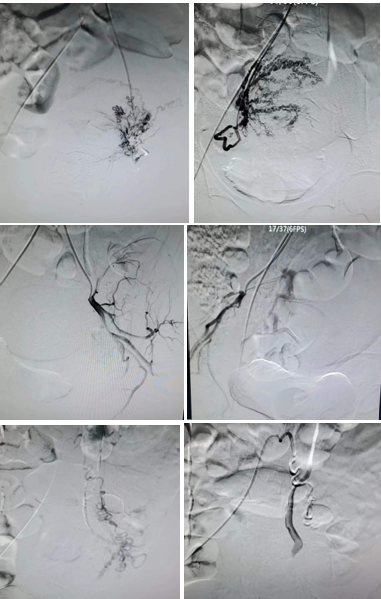

患者38岁,既往3次剖宫产史,2次人流史。本次妊娠16周+5天,B超提示胎盘下缘后方与子宫前壁下段分界欠清,可疑胎盘植入。产科医师评估引产风险极大,有发生子宫破裂、难治性产后出血、子宫切除甚至危及生命的可能。陈思攀医生立即组织产科、心内科和介入手术室,组成MDT团队,讨论决定进行引产前子宫动脉栓塞术,以最大程度减少引产术中出血等。由于患者妊娠次数较多,子宫动脉错综复杂,经过两个小时的介入手术,患者多支子宫供血动脉栓塞满意。次日顺利施行钳刮引产术,出血量仅为260ml(预估未栓塞情况下,出血量至少800ml以上),现患者已顺利康复出院。

帮助周至县人民医院成功开展的子宫动脉栓塞术,填补了周至地区在救治产后出血介入方面的技术空白,极大提高了该院急危重孕产妇的救治能力和水平,保障了孕产妇安全。